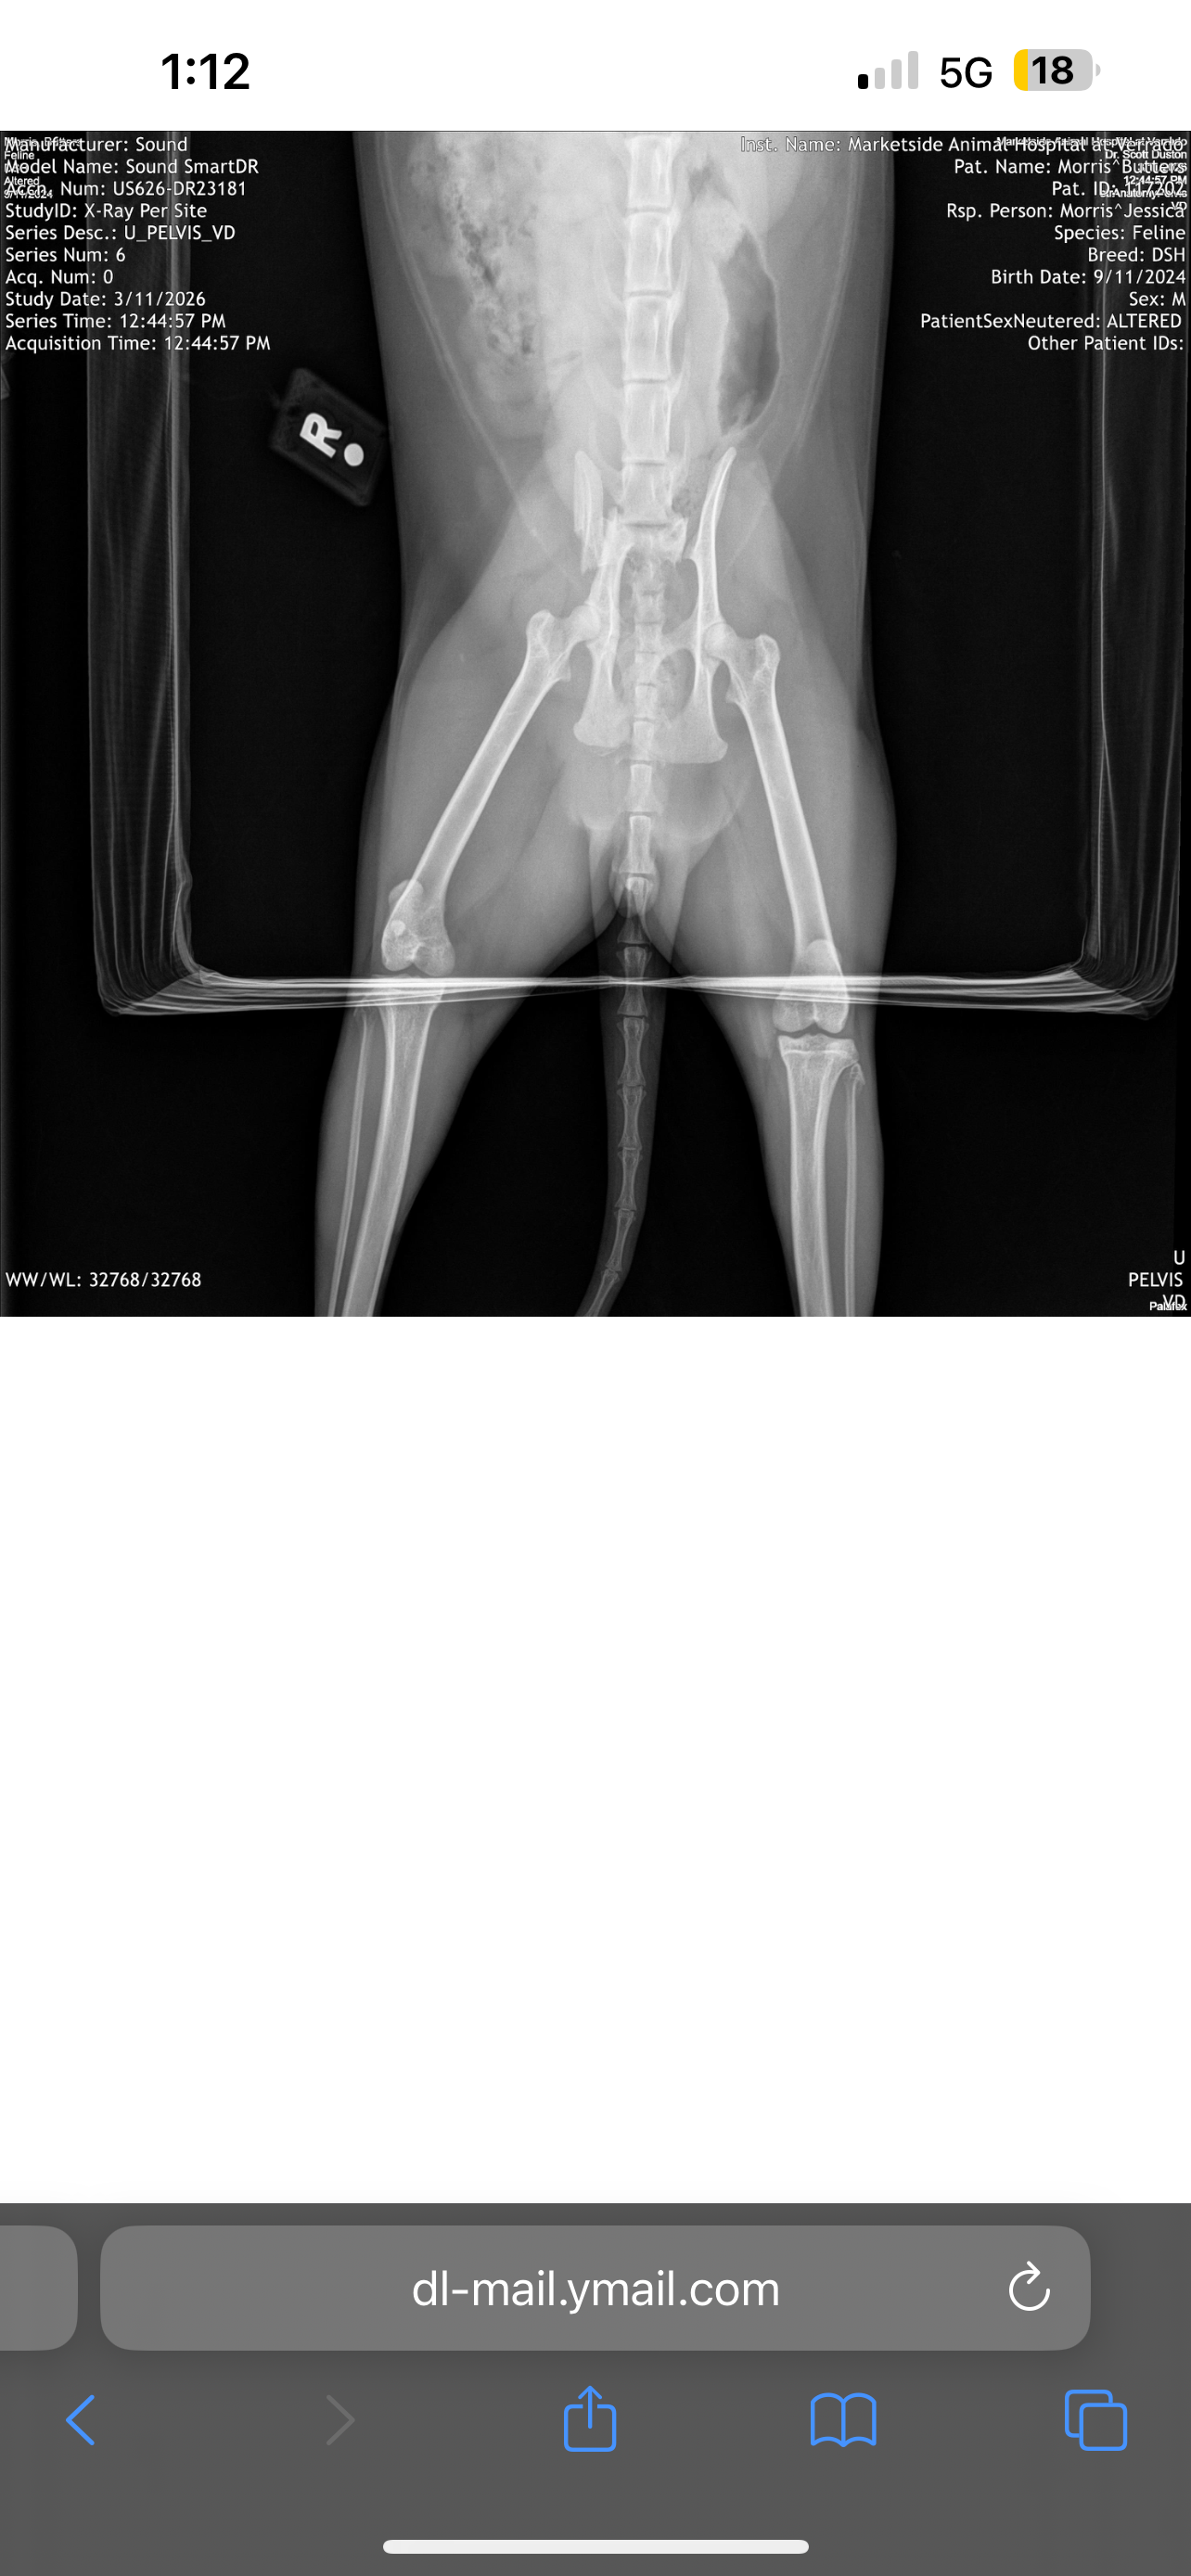

Please help save my cat Butters. Butters is basically my service animal helping me survive through Alcoholism recovery. He is very special to me, he is my child. I even taught him to say “mama”. He got ran over and both hips are broken. He will need surgery or to be put down. I am doing everything I possibly can to keep him with us. I do not want to put him down. I have taken him to the animal hospital for X-rays and surgery will cost up to 5k. Please help. Anything is appreciated. Thank you.